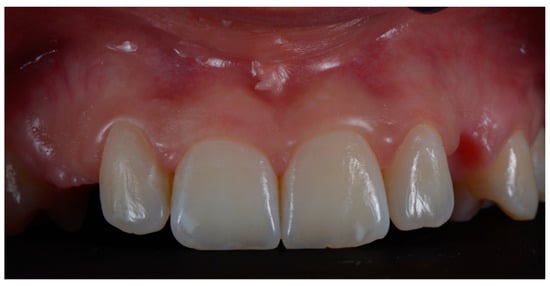

:1. Introduction

2. Materials and Methods

2.3. Surgical and Prosthetic Workflow

2.4. Outcome

3. Results